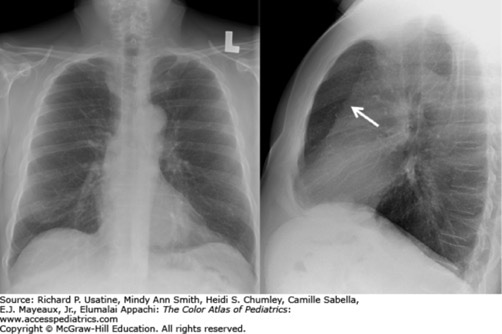

Answer: Acute asthma exacerbation with increased lung volumes on chest x-ray. The lateral projection reveals enlargement of the retrosternal clear space (arrow). (Used with permission from Carlos Santiago Restrepo, MD.)

From Usatine RP, Smith MA, Chumley HS, et al. The Color Atlas of Pediatrics. New York, NY: McGraw-Hill; 2015.